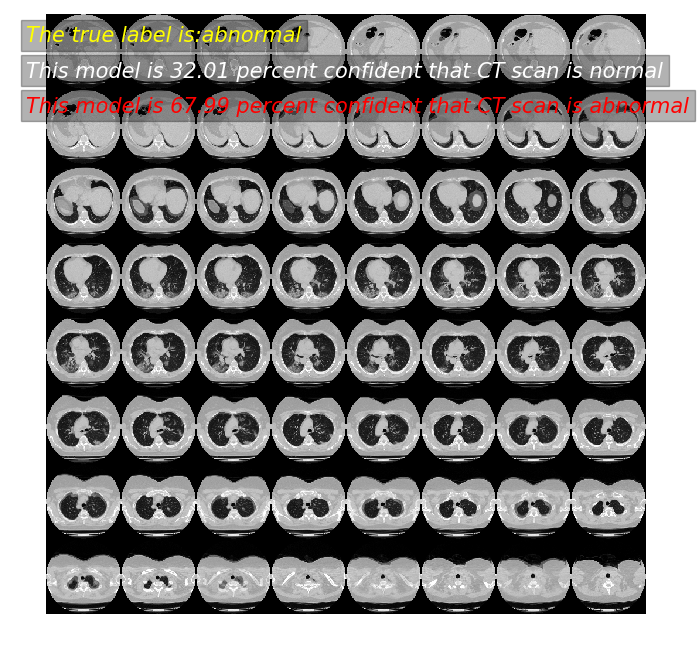

9、模型预测

对模型进行预测,展示效果。

predictor(2)

模型预测: 43.85 概率,这张CT normal

模型预测: 56.15 概率,这张CT abnormal

真实标签为: abnormal

predictor(11)

模型预测: 32.01 概率,这张CT normal

模型预测: 67.99 概率,这张CT abnormal